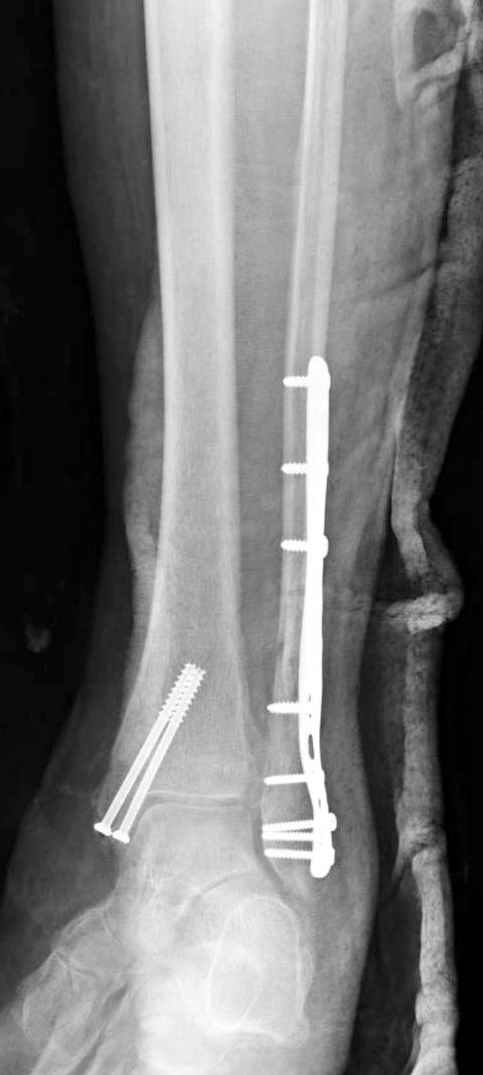

Здесь финальный снимок 73 летней с

сопутствующей шизофренией, латерально бридж

пластину (соединили дистальный конец с диафизом не трогая место перелома) и медиально перкутанно

двумя шурупами. В этам случае без гипса не

обойтись.

Точно, для идеальной репозиции надо открыть передний и задний углы медиальной лодыжки,

сделать ревизию сустава, очистить, убрать интерпозицию, потом только зафиксировать.

Как заметил, по рентгенограмме медиальная лодыжка не очень идеально репонирована. Больная кроме шизофрении страдала другими соматическими заболеваниями, и во время операции от анестезиолога получил рекомендацию поторопиться, поэтому решили закрыто, а так тенденция лечить

открытым методом.